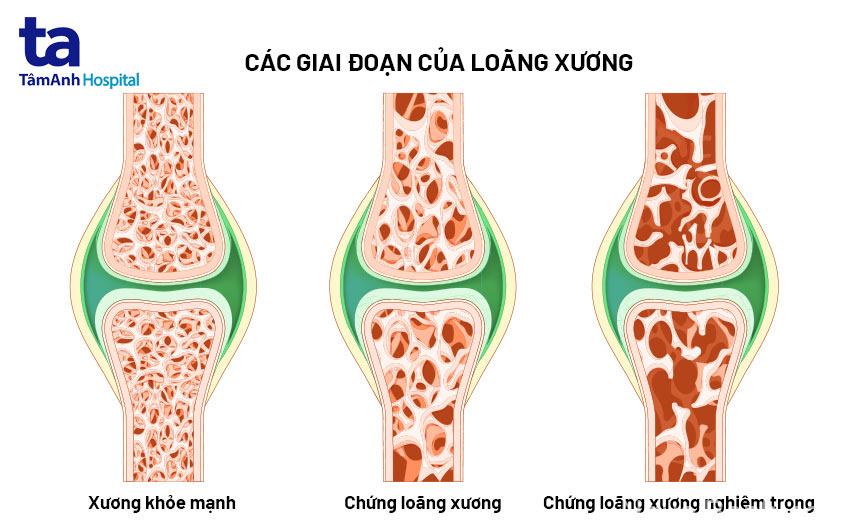

Càng lớn tuổi, mật độ xương sẽ thấp hơn và cấu trúc xương cũng trở nên giòn & dễ vỡ; khiến cho người lớn tuổi dễ mắc bệnh loãng xương. [1]

Người lớn tuổi thường có mật độ xương thấp hơn người trẻ hay người khỏe mạnh

Thêm nữa khi về già, sụn khớp sẽ dần mất nước làm suy giảm khả năng cản lực ma-xát tác động lên xương. Dây chằng & các mô liên kết khác của sụn cũng trở nên kém đàn hồi, khiến biên độ hoạt động của khớp giảm, khi có tác động mạnh có thể gây viêm và đau khớp. [2]

Các giai đoạn của thoái hóa sụn khớp